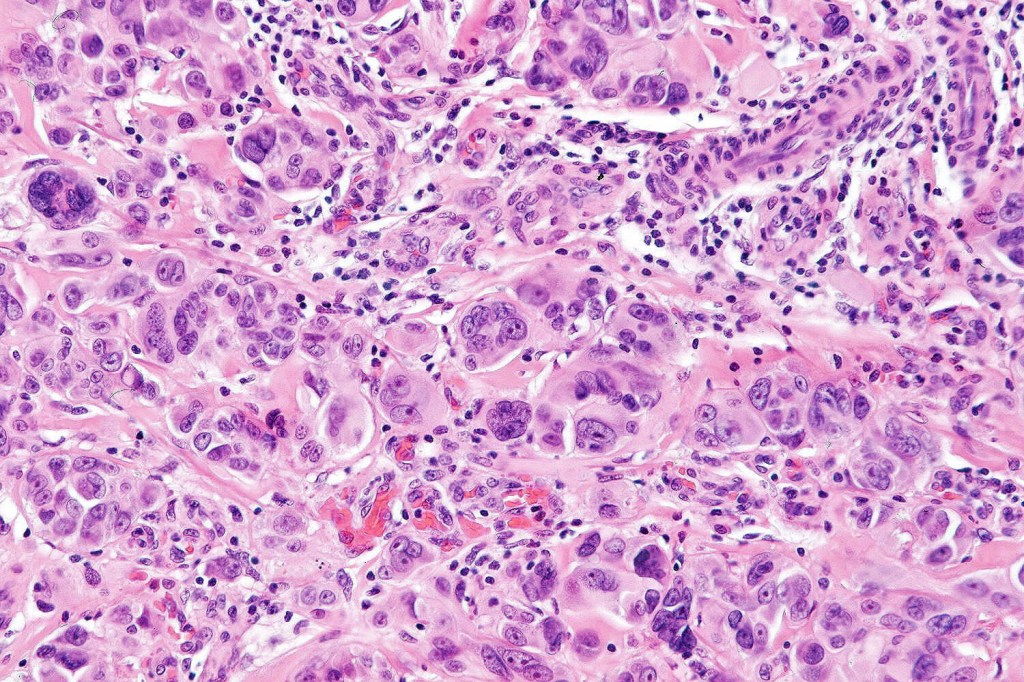

These are very rare variants of amelanotic or virtually amelanotic melanoma where a primary melanoma or a metastasis shows partial (DN) or complete loss (UN) of recognizable histological and immunohistochemical features. The histology may lead the pathologists to consider lymphoma, sarcoma, anaplastic carcinoma or a small cell tumor. Some examples of rhabdoid melanoma & melanoma with heterologous differentiation probably belong in this category. Ultimately, if there is no identifiable/recognizable primary tumor, diagnosis may only be comfortably made with next-generation sequencing. In the cases presented below, immunohistochemistry was of value in determining the melanoctic nature of the tumor (undifferentiated melanoma).